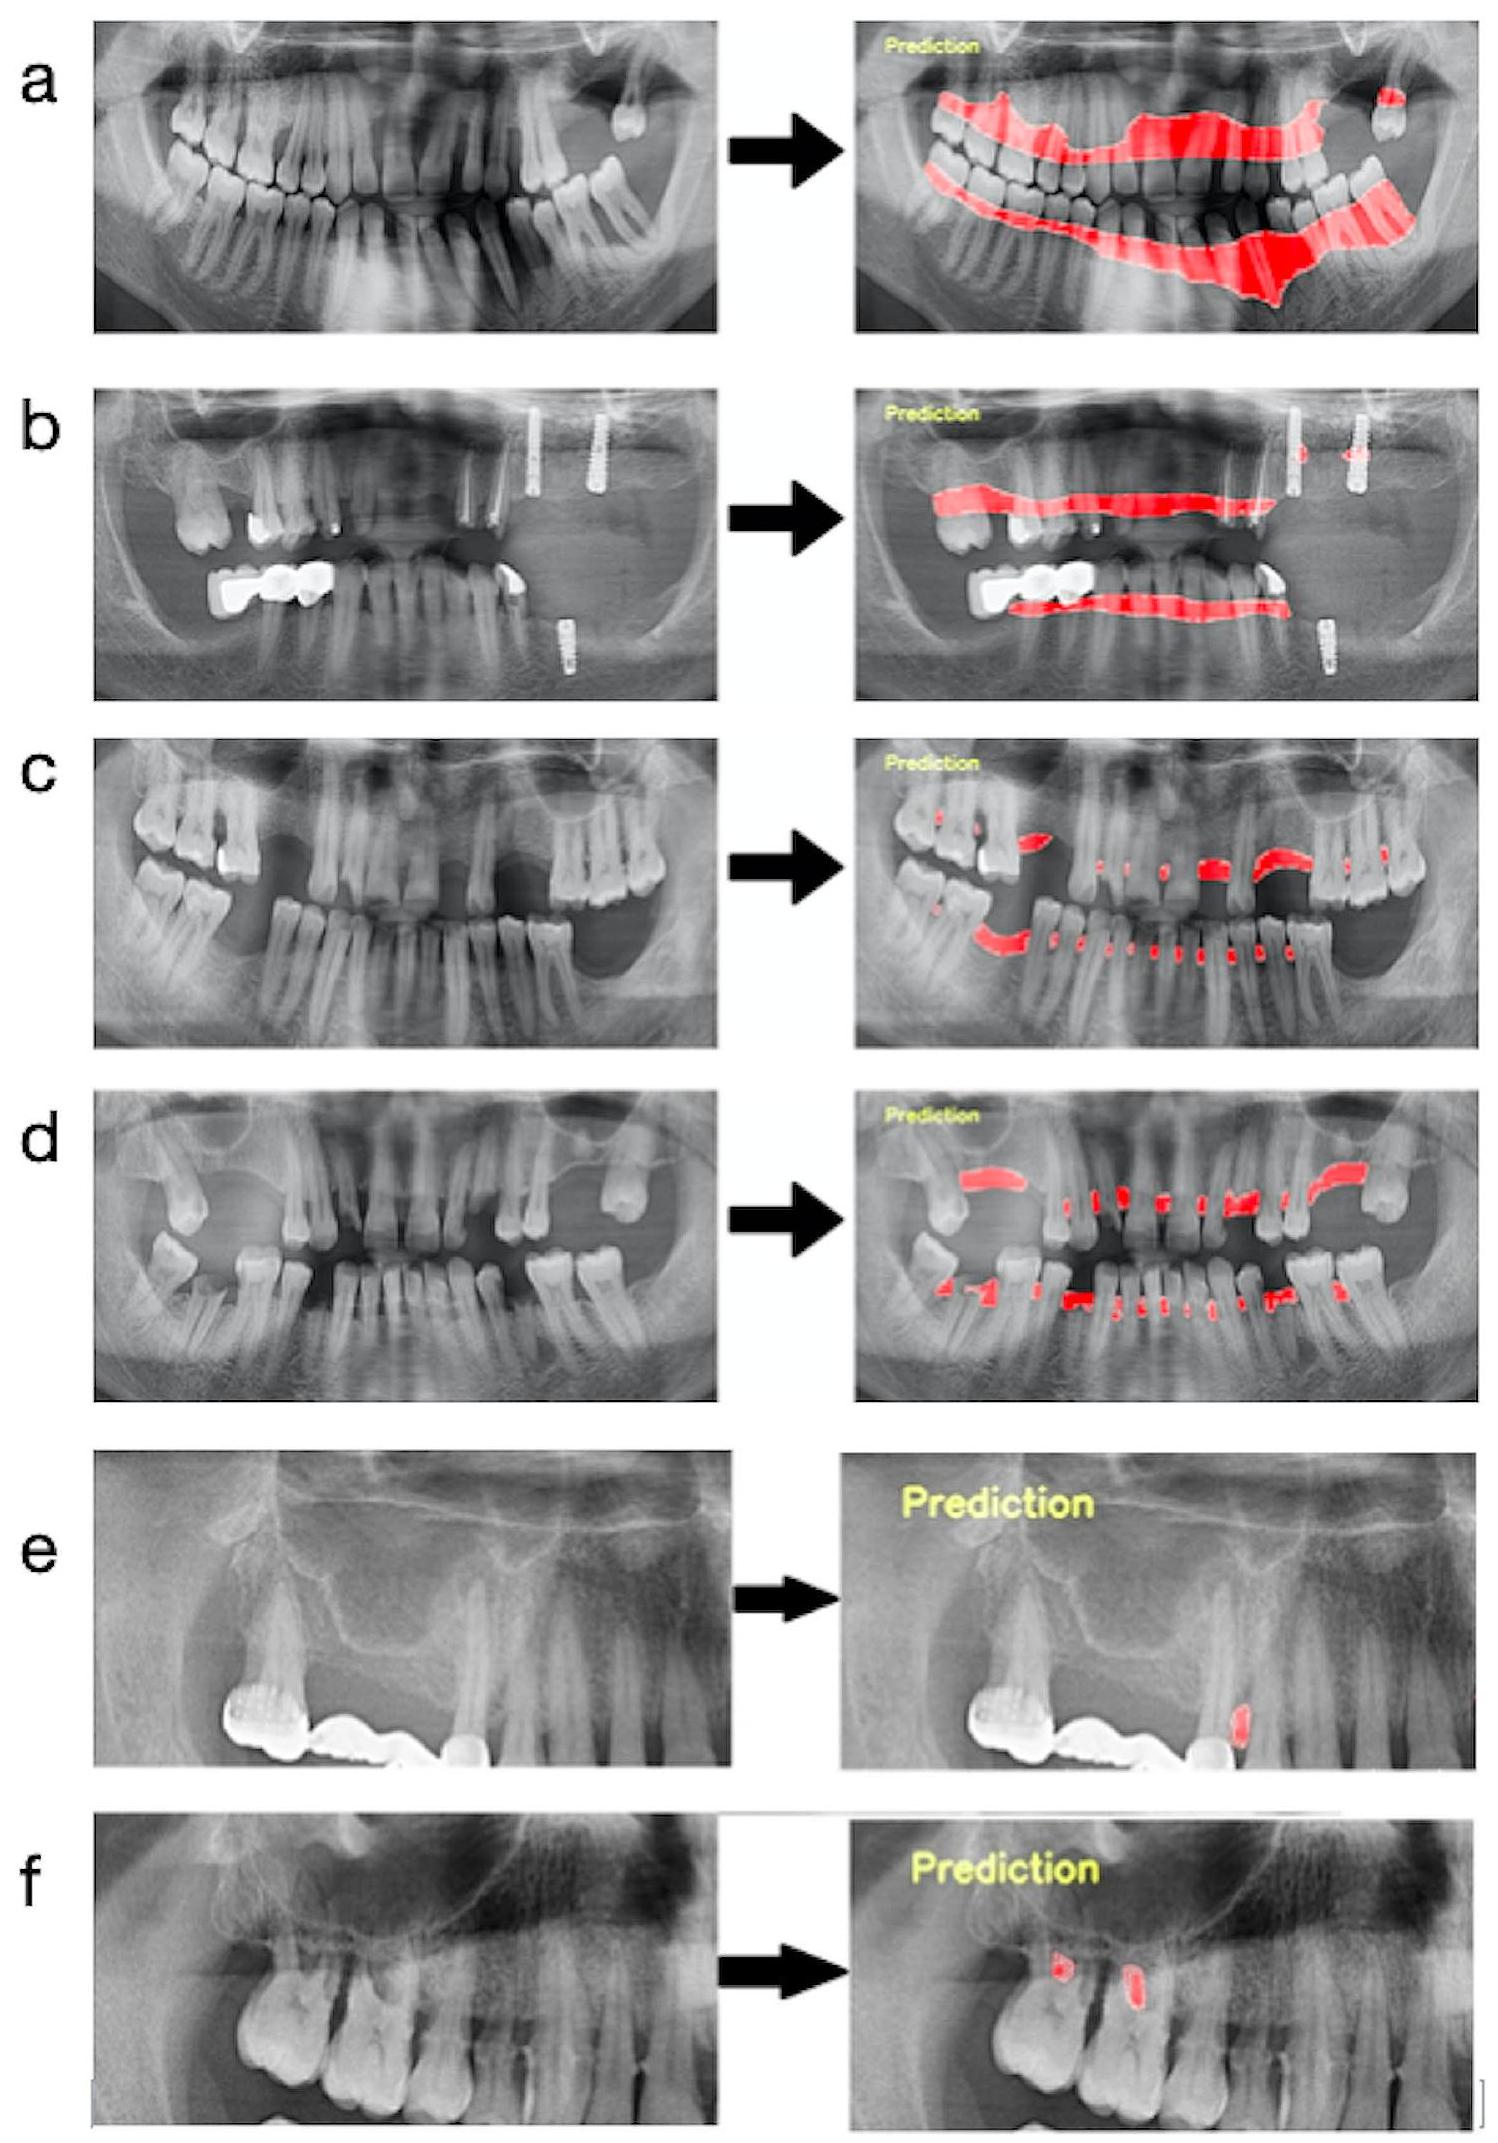

pixels. Panoramic radiographs to be used in the data sets created for developing the furcation defect model were cropped to 4 (left mandible, right mandible, left maxilla, and right maxilla). Since furcation defects were only seen in multi-rooted molars, it was aimed to focus more on the relevant areas in this way. The radiographs to be used in other parameter models were not

cropped but used as a whole. Images that do not have the related parameter label were excluded from the main data sets of that parameter (Figs. 2 and 3). In line with these criteria, 1121 panoramic radiographs for total alveolar bone losses, 1120 panoramic radiographs for horizontal bone losses, 828 panoramic radiographs for vertical bone losses, and 1941 cropped panoramic radiographs ( 890 panoramic radiographs) for furcation defects were included in the main datasets (Table 1; Fig. 3). - Training, Validation, and Testing Data: The main datasets were created by combining all panoramic radiographs containing the relevant parameter labels for each parameter. Then these main datasets were split as a training set (

Outcomes

Observations

aims to automatically evaluate panoramic radiographs by an AI system and to determine the success of the related system in detecting periodontal disease findings on radiographs. The results of this study showed that AI systems can be a decision-support mechanism for dentists

was used in this study for labeling. The segmentation method we use is a much more advantageous method since it determines the defective area with its borders. Because it provides more detailed information to the dentist to determine the severity of the disease and to plan the treatment in the next process. In addition, in this method, the defect area is processed like a detailed map and provides more advanced diagnostic support visually. On the other hand, when two studies were compared in detail, it was seen that they used multiple observers, and two different AI architectures (U-Net and Yolo-v4), and included the severity of the disease in their assessment.